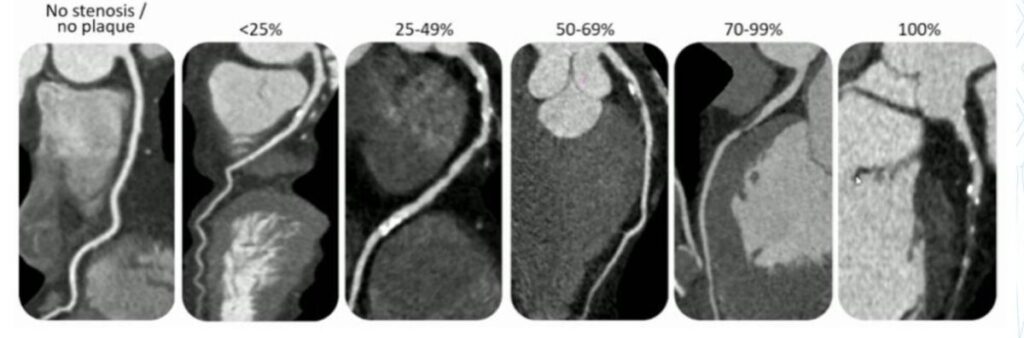

This is a radiological test during which contrast dye is injected into the vein and images of the blood vessels around the heart (coronary arteries) are acquired a few seconds later. This test assesses for plaque build-up and narrowing of the coronary arteries. It picks up early coronary artery disease from which you may have no symptoms of, to more advanced disease for which you may need more definitive treatment such as stents placed or bypass surgery.